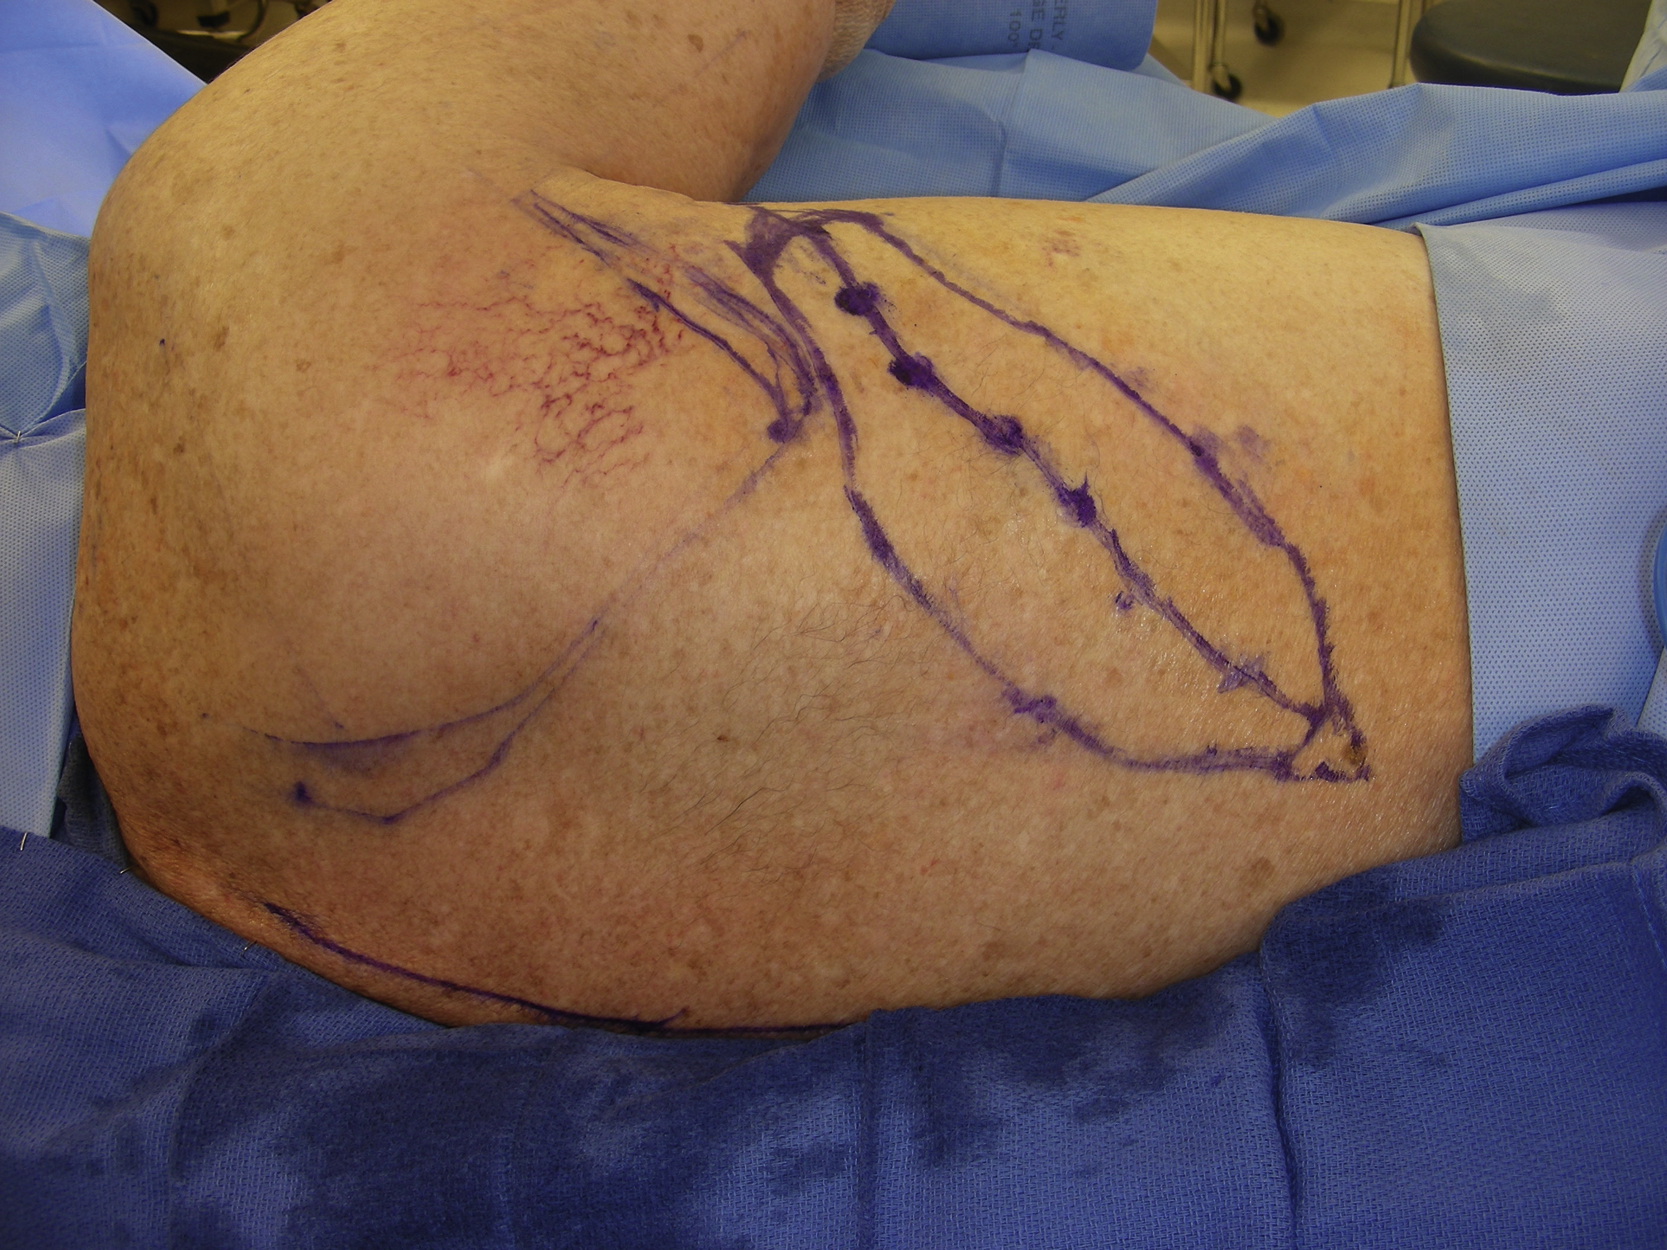

The pedicled parascapular fasciocutaneous flap was designed over the right back ( Fig. 15.4 ). A handheld Doppler was used to map the descending branch of the circumflex scapular vessel. An 8 × 5 cm skin paddle was marked on the back because it could easily reach to the right axilla without any tension. The proposed skin incision was infiltrated with 1% lidocaine with 1:100,000 epinephrine.